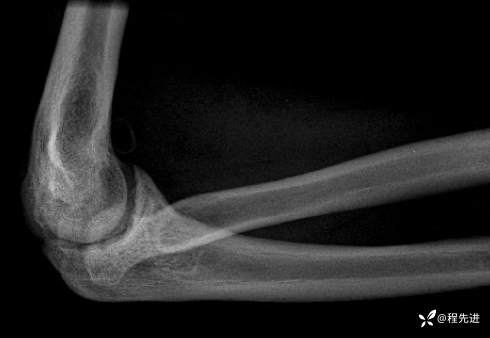

右肘关节正侧位DR:

img